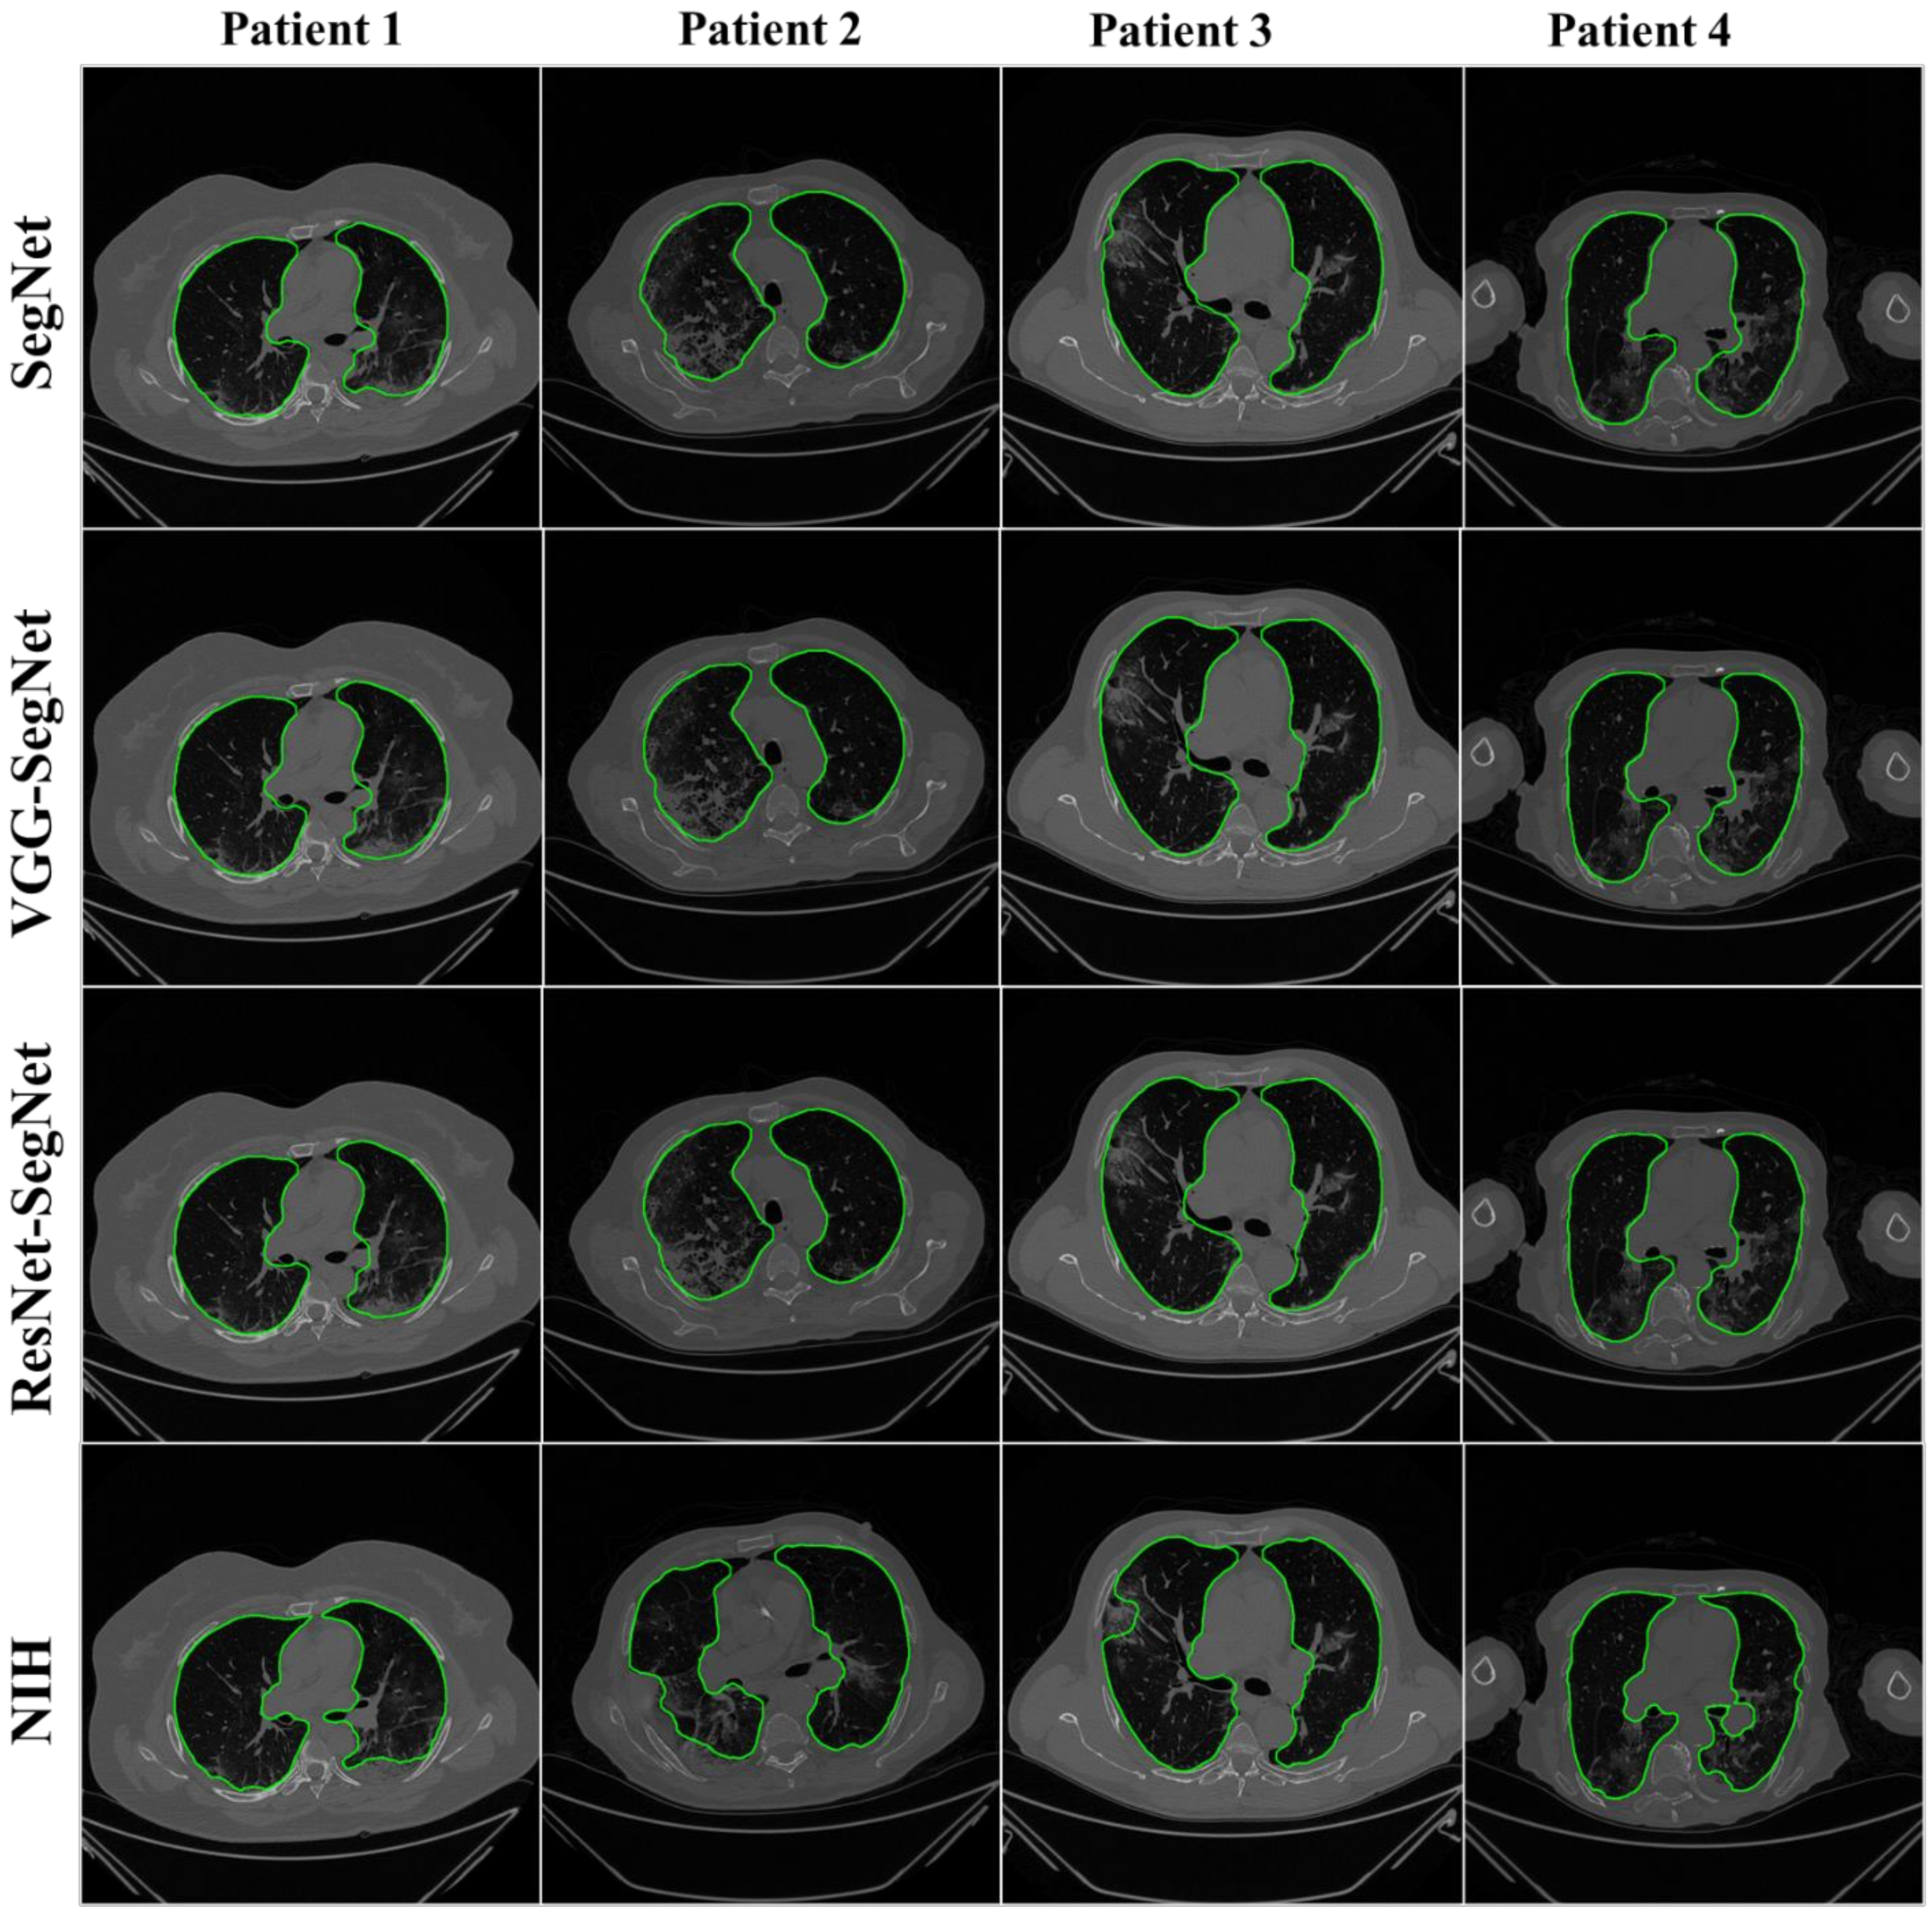

4.2.1. Visualization of Lung Boundary and Regional Lung Error